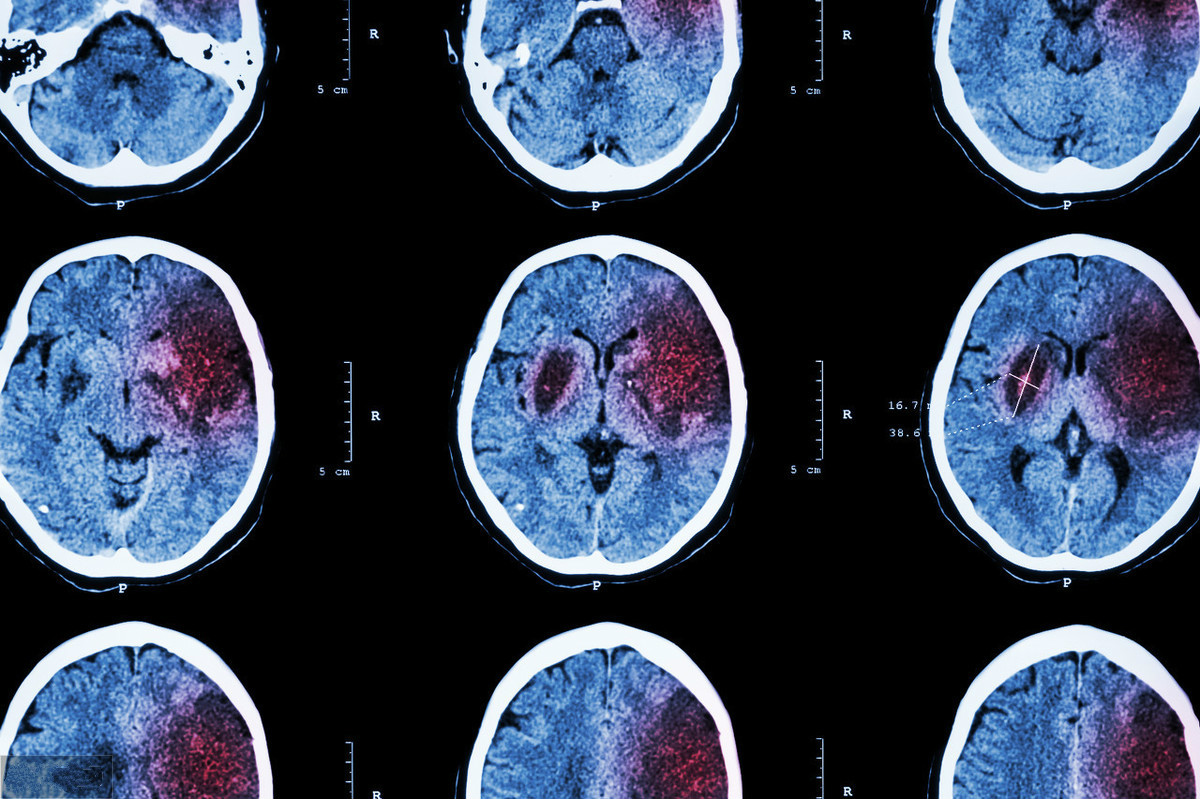

如果患者存在腦溢血,建議這些患者一定要到醫(yī)院進(jìn)行就診,患者容易出現(xiàn)發(fā)熱,頭痛,肢體活動(dòng)障礙,惡心嘔吐,口角歪斜等癥狀。這些患者需要完善頭顱CT等檢查,以進(jìn)一步明確患者是否存在腦溢血以及腦出血的部位和腦出血量。

如果患者存在少量的腦出血,這些患者通過藥物進(jìn)行積極治療以后,大部分患者預(yù)后會(huì)比較好。如果患者存在大量的腦出血或者腦干等部位的出血,患者病情會(huì)非常的嚴(yán)重,這些患者如果沒有及時(shí)治療,很有可能會(huì)出現(xiàn)生命危險(xiǎn)。